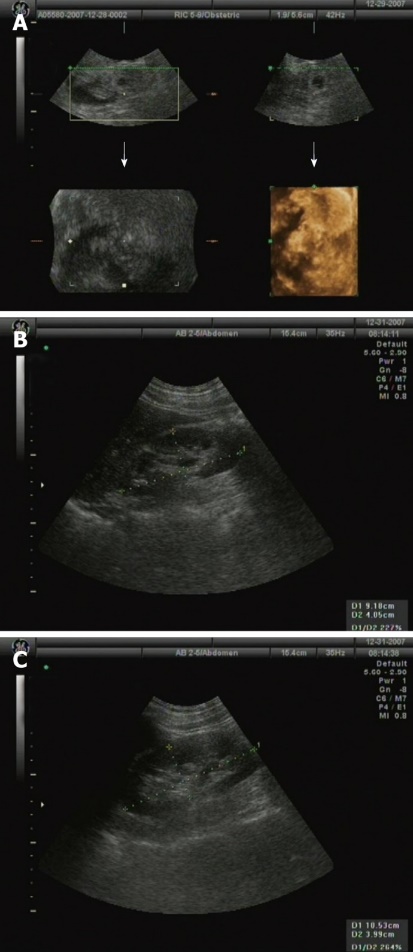

Υπερηχογράφημα κοιλίας και νεφρών χωρίς ανεύρεση μάζας ή συλλογής υγρού (Α), φυσιολογική δομή αριστερού (Β) και δεξιού (Γ) νεφρού (Ευγενική παραχώρηση Dr. V. Penopoulos)